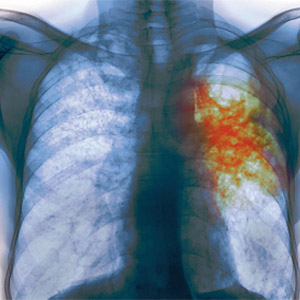

Одним из путей выявления туберкулеза является флюорография

(рентгенография) легких. Рентгенофлюорографическое обследование проводится в

17 лет, в последующем не реже 1 раза в 2 года для всего населения и ежегодно для

групп риска